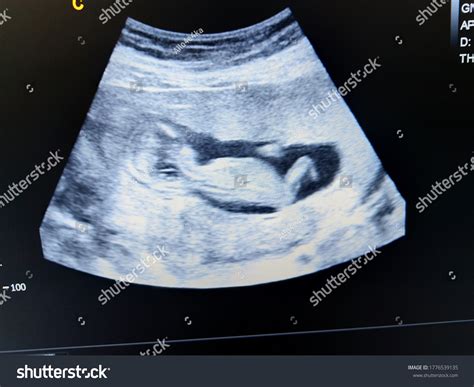

A 14 week ultrasound is typically performed between 13 weeks and 14 weeks of pregnancy. It is often referred to as the “nuchal translucency” scan because it measures the thickness of fluid behind the baby’s neck. This measurement, along with other factors, can help assess the risk of certain chromosomal abnormalities, such as Down syndrome.

During the 14 week ultrasound, you will lie on an examination table with your abdomen exposed. The technician will apply a gel to your belly and use a transducer to capture images of your baby. The procedure is painless and usually takes about 20-30 minutes.

The results of a 14 week ultrasound can provide important information about your baby’s health. The nuchal translucency measurement, combined with maternal age and other factors, is used to calculate the risk of chromosomal abnormalities. It’s important to note that this scan is a screening tool and not a diagnostic test. If the results indicate a higher risk, further testing, such as amniocentesis or chorionic villus sampling (CVS), may be recommended.

During a 14 week ultrasound, several key findings are typically assessed:

Finding Description

Heartbeat The baby’s heartbeat should be strong and regular, usually between 120 and 160 beats per minute.

Nuchal Translucency This measurement helps assess the risk of chromosomal abnormalities. A thicker measurement may indicate a higher risk.

Anatomy The technician will check for the presence of all major organs, including the brain, heart, stomach, and kidneys.

Placenta The position of the placenta will be noted to ensure it is not covering the cervix, which could lead to complications later in pregnancy.

Amniotic Fluid The amount of amniotic fluid will be assessed to ensure it is within normal ranges.